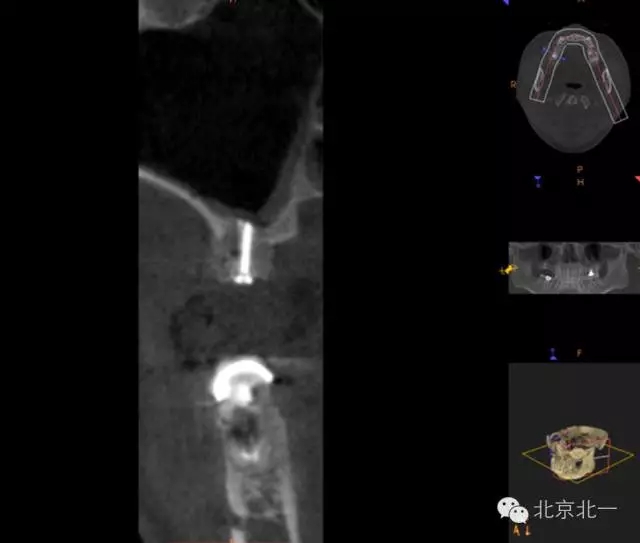

圖十九:手術(shù)后當(dāng)天CBCT

圖二十-二十二:ONLAY植骨半年后

圖十六:植入植體